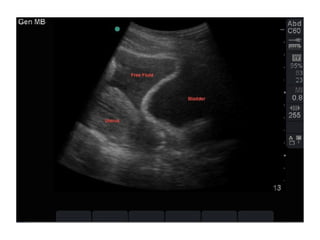

• 7 years old Girl

• Front seat passenger

• FAST scan: Free fluids in the pelvis

• Haemodynamically stable

• Admitted under paediatrics

• CT abdomen next day: No intra-abdominal injuries

Trauma Call: 005